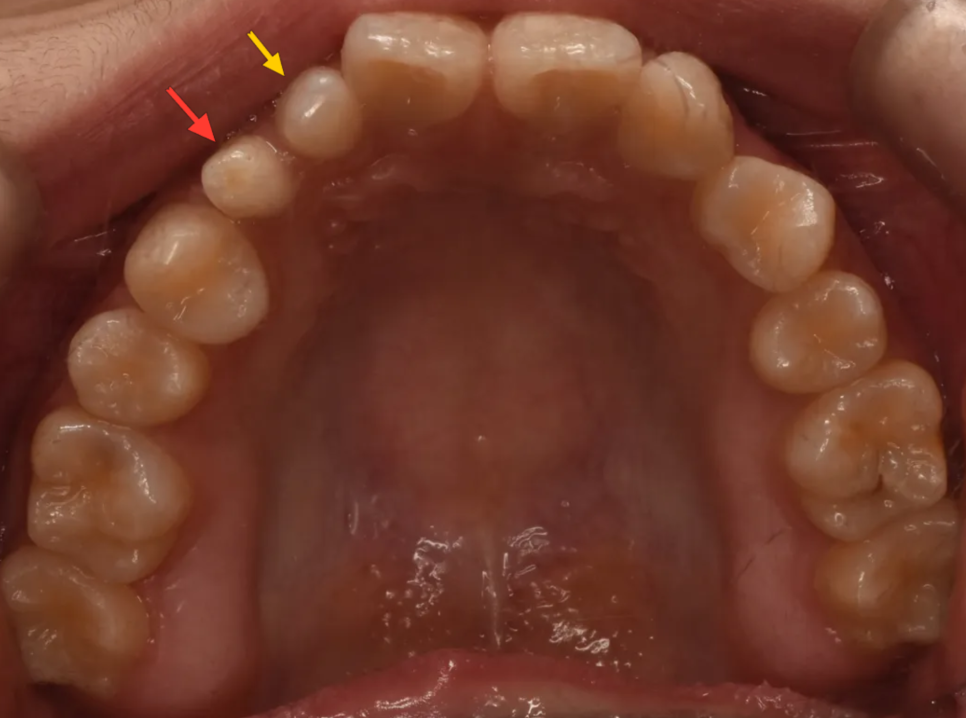

다음으로 눈에 띄는 것은 있어야 할 이가 없는 경우(결손치)인 경우입니다. 아래 그림에서 표시된 이는 작은앞니(측절치)위치에 있지만 실제로는 송곳니입니다. 즉 작은앞니가 없는 공간으로 뒤쪽에 있던 송곳니가 밀려나온 경우입니다. 그리고 공간이 남기 때문에 그 뒤의 작은어금니가 공간을 채우면서 회전되어 있는 것이 보입니다.

노랑: 결손된 측절치 위치로 밀려나온 송곳니 / 파랑: 공간을 채우느라 회전한 작은어금니